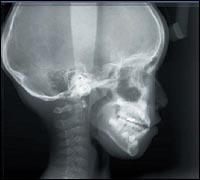

Система кодирования зон упрощает процесс осуществления настроек и позиционирования пациента Множественные томограммы выбранной области можно получить, используя систему кодирования зон и панели управления жидкокристаллического дисплея. Вы будете изумлены простотой и легкостью этой операции. Сначала работайте в программе стандартной панорамной съемки с использованием кассеты с калибровкой кода зоны. Затем выберите номер кода той зоны, где необходимо получить томограммы путем формирования панорамного снимка. Установите панель управления жидкокристаллическим дисплеем для программирования томографа и затем введите номер кода зоны. Снова позиционируйте пациента, используя функцию автоматического фокуса, и удерживайте кнопку излучателя для автоматического фокусирования на выбранном участке томограммы. Рентген оборудование компании J.Morita: эталон среди дентальных цифровых рентгеновских аппаратов При этом отпадает необходимость в сканировании компьютерным томографом, который облучает пациента значительной дозой рентгеновского облучения! Позиционирование пациента для получения томограммы соответствует той же самой процедуре, что и для проведения панорамной съемки. Нет никакой необходимости принуждать пациента принимать неестественную и неудобную позу!